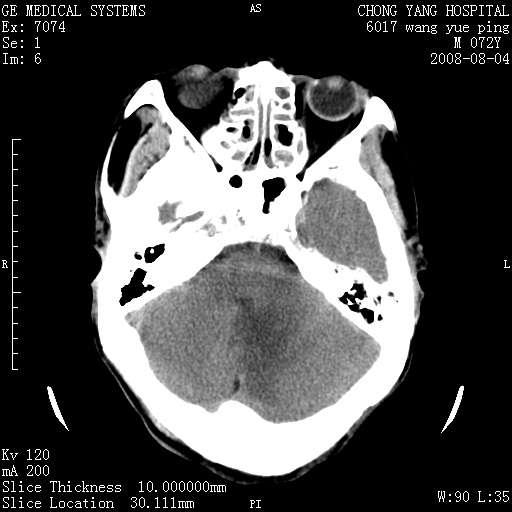

标题: CT14987:M72Y,头痛头昏,BP220/110. [打印本页]

标题: CT14987:M72Y,头痛头昏,BP220/110.

1)考虑左侧小脑脑梗塞。2)脑白质病。3)脑萎缩。4)双侧鼻腔新生物(息肉?)并阻塞性副鼻窦炎。

1.左侧小脑大面积梗塞;2.左侧基底节区腔梗;3.白质疏松;4.脑萎缩;5.慢性副鼻窦炎

小脑左侧病灶呈扇形分布,增强后未见明显瘤体样节结影,病变区未见强化。

支持:左侧小脑脑梗塞梗塞表现

另:脑白质病。脑萎缩。双侧鼻腔新生物(息肉?)并阻塞性副鼻窦炎。

1)考虑左侧小脑脑梗塞,建议治疗后复查除外其他,左基底节区腔隙性脑梗塞2)脑白质变性3)脑萎缩。4)双侧鼻腔新生物(息肉?)并阻塞性副鼻窦炎。